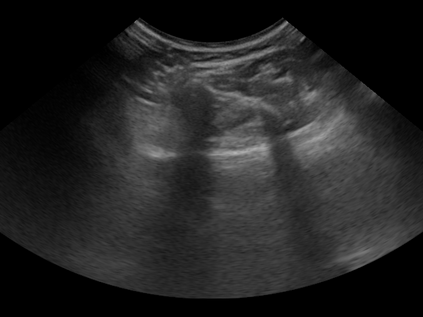

Three-dimensional (3D) freehand ultrasound (US) reconstruction without a tracker can be advantageous over its two-dimensional or tracked counterparts in many clinical applications. In this paper, we propose to estimate 3D spatial transformation between US frames from both past and future 2D images, using feed-forward and recurrent neural networks (RNNs). With the temporally available frames, a further multi-task learning algorithm is proposed to utilise a large number of auxiliary transformation-predicting tasks between them. Using more than 40,000 US frames acquired from 228 scans on 38 forearms of 19 volunteers in a volunteer study, the hold-out test performance is quantified by frame prediction accuracy, volume reconstruction overlap, accumulated tracking error and final drift, based on ground-truth from an optical tracker. The results show the importance of modelling the temporal-spatially correlated input frames as well as output transformations, with further improvement owing to additional past and/or future frames. The best performing model was associated with predicting transformation between moderately-spaced frames, with an interval of less than ten frames at 20 frames per second (fps). Little benefit was observed by adding frames more than one second away from the predicted transformation, with or without LSTM-based RNNs. Interestingly, with the proposed approach, explicit within-sequence loss that encourages consistency in composing transformations or minimises accumulated error may no longer be required. The implementation code and volunteer data will be made publicly available ensuring reproducibility and further research.